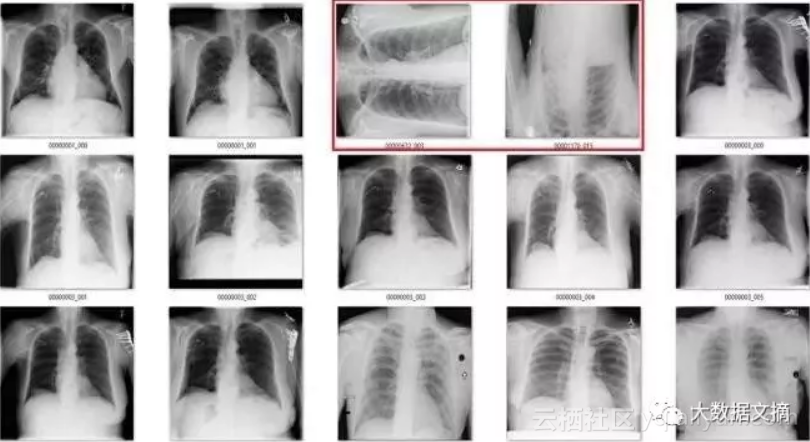

为了说明这一点,我们来看一个来自CXR14的简单例子。在数据集中的正常胸部X射线中,有一些图像经过旋转(这些旋转并未标识在标签中,因此我们不知道哪些是旋转过的)。它们有可能被左右旋转了90度,或180度(颠倒)。

我们建立一个正常图像的数据集,旋转其中的一半,并相应地标记它们。

在我的例子中,我选择了4000个训练数据,其中2000个是经过旋转的,此外,我还选择了2000个作为交叉验证数据,其中1000个是经过旋转的。

所以,我们的最后一步是在整个数据集上运行模型,进行预测,然后根据预测结果排除那些旋转的图像。由于数据中被旋转过的图像很少,所以我可以一张张检查那些被预测为异常的图像。

该模型一共标记出了171个“旋转”的图像。有趣的是,它实际上作为一个“异常”检测器,识别出许多在非胸部X光的图像。这也不难理解,因为这个模型可能是在学习解剖学的标志。任何异常的东西,如旋转的图像或者是其他身体部位的X射线图像,都不具有正常图片应有的特征。真是意外收获!

在171个被标记为“旋转“的图像中,有51个是实际上旋转过的正面胸部X射线图像。鉴于图片旋转发生的概率非常低(120,000个案例中有51个),这已经是极低的假阳性率。